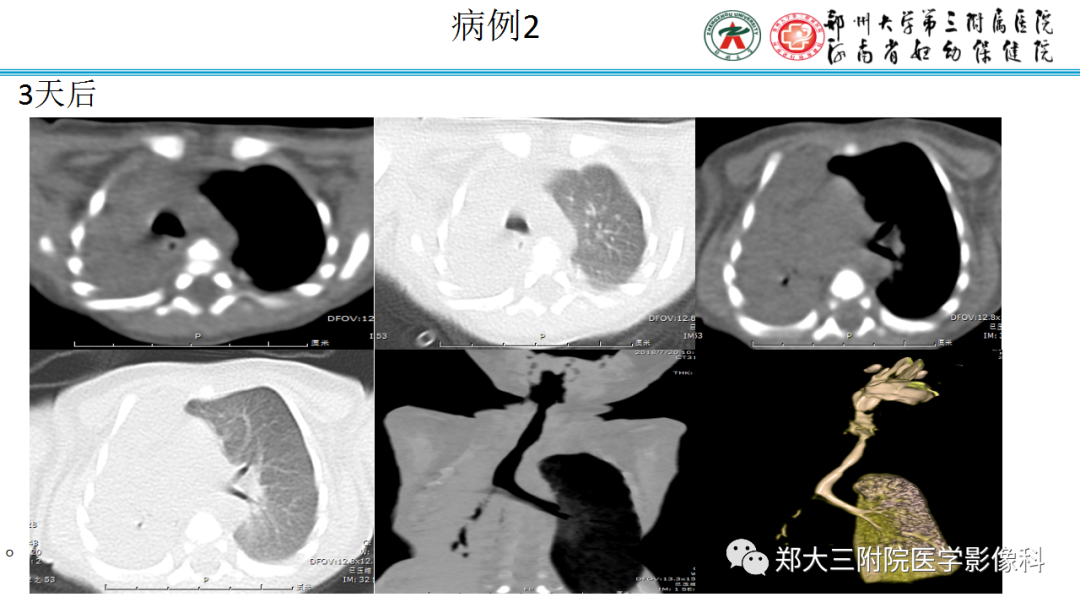

下图2例为隐源性机化性肺炎(COP)的慢性实变。

胸膜下及周围分布有斑片状实变,鉴别诊断与上述相同。